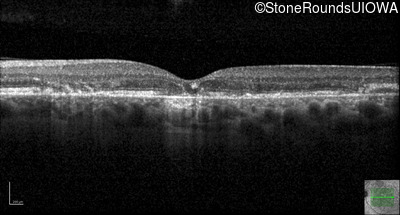

Optical Coherence Tomography - Right - 20/20 -1 sc

Exemplar / OCT Stack